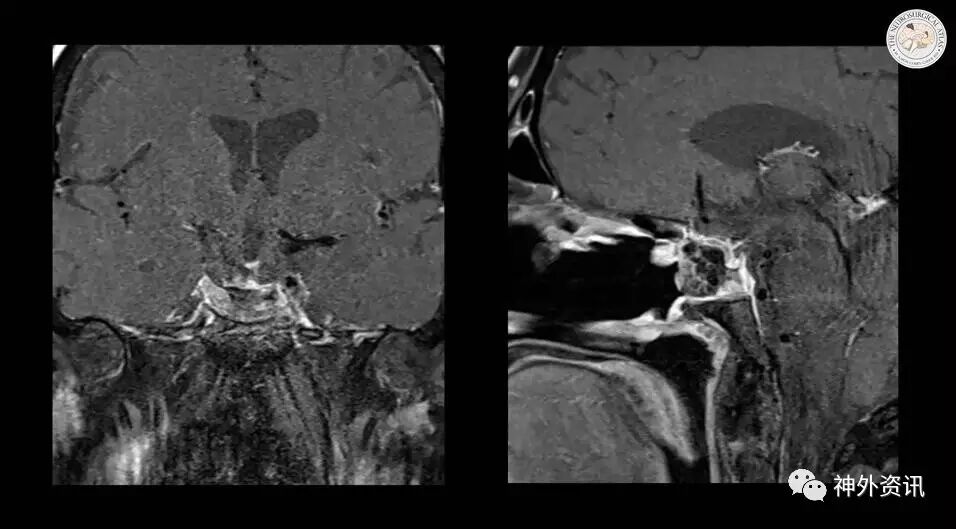

图18. 术后MR提示病灶全切,视路减压充分。患者术后视力明显改善。

Using some glue to further buttress the whole construct.And the postoperative MRI in this case demonstrated the desirable result and gross total removal of the mass with adequate decompression of the optic apparatus. This patient’s vision improved significantly postoperatively. Thank U.

使用胶水进一步支撑整个重建物。术后MR提示结果理想,病灶全切,视路减压充分。患者术后视力明显改善。谢谢。